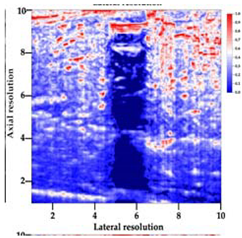

3.3. B-Mode Images

3.5. Echogenicity

4.1. Ultrasonography and Aerogel Dimensional Analyis

| Aerogel Type | US Image | Normalized Intensity Map | 3D Intensity Map | |

|---|---|---|---|---|

| 1 | Muscle |  |  |  |

| 2 | X-silica |  |  |  |

| 3 | X-silica-La2O2S:Eu |  |  |  |

| 4 | SMPU-Mix-14 |  |  |  |

| 5 | SMPU-Mix-18 |  |  |  |

| 6 | BRF-CA |  |  |  |

| 7 | ARF-CA |  |  |  |

| 8 | X-Ca-Alg-2 |  |  |  |

| 9 | X-Ca-Alg-1 |  |  |  |